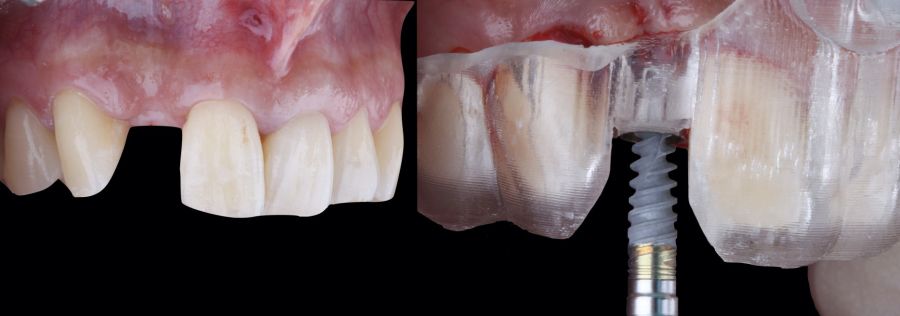

1.2 Treatment

• Phase I: atraumatic extraction of the root remnant 1.2 was performed, followed by curettage of the granulation tissue. Subsequently, the alveolus was filled with an inorganic bovine bone graft (0.25–1mm) combined with autologous platelet- and leukocyte-rich fibrin. Finally, the edges were approximated and sutured with four simple stitches from the vestibular mucosal margin to the palatal aspect. Subsequently, the patient continued using her removable partial denture as a provisional restoration (Figure 1).

* Phase II: healing proceeded without complications. After 5 months from the alveolar preservation surgery, guided implant surgery was planned at position 1.2 (Figure 2). For this purpose, a DICOM file from cone beam computed tomography (CBCT) and an STL file obtained from scanning with an intraoral optical scanner were used. Using this information, a dental support surgical guide was fabricated (Figure 3). The surgical guide was anchored onto the teeth and guided the preparation of the implant bed and the placement of the implant. The guided surgery technique consisted of flap surgery, preparing and inserting the implant (3.5 x 11.5 mm) according to the standardised Nobel Active® guided surgery protocol (Nobel Biocare AB, Gothenburg, Sweden). Once implant 1.2 was placed,a gingival graft composed of epithelium and connective tissue from the palatal masticatory mucosa was obtained. Subsequently, the superficial epithelial layer of this graft was deepithelialised extraorally using a 15C scalpel blade in order to obtain a connective tissue graft from the underlying layer18.

The de-epithelialised graft was inserted and

positioned buccally and occlusally using horizontal mattress sutures with 5-0 non-resorbable suture (Figure 4)19.